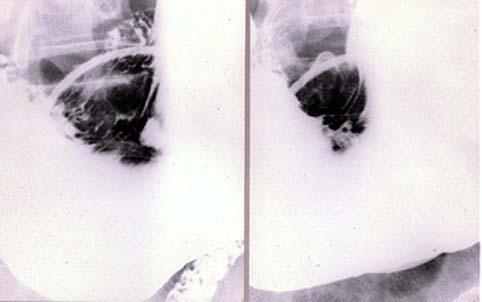

clasificación del pacienteTumor Epitelial Maligno/Adenocarcinoma

parte(separada por órganos)estómago(región)/ángulo

método de exámenRayos X

clasificación ectoscópica de tumoresTipo 0(tipo superficial)/Tipo IIc(IIc)

diámetro mayor del tumor25 - 29

grado de penetraciónm